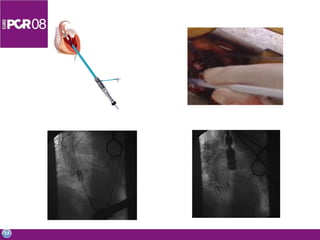

Subclavian access (Corevalve TM) Short delivery distance Painless Local anesthesia Retrograde approach

Cath lab Vascularaccess Catheterization Angiography PTCA Non coronary interventions Material inventory Simple diagnostics done in the OR

Subclavian access (CorevalveTM) Short delivery distance Painless Local anesthesia Retrograde approach